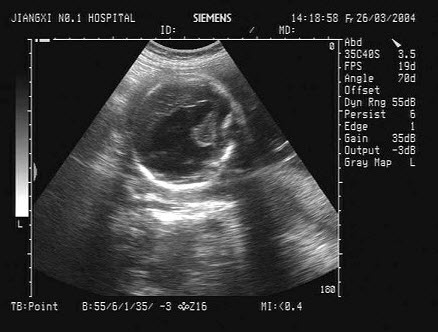

一孕妇,孕28周,根据胎儿头部B超声像图,最可能的诊断为()

A.胎儿脑积水

B.无脑儿

C.脑膜脑膨出

D.正常胎儿

E.透明隔囊肿